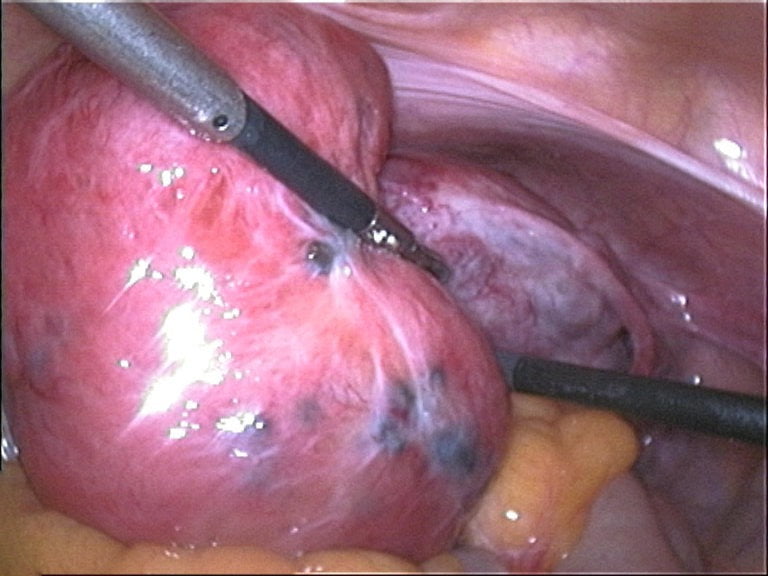

Imagem de laparoscopia, demonstrando um útero aumentado e amolecido, achado comum na adenomiose, associado a focos de endometriose em sua superfície. Fonte da imagem: https://commons.wikimedia.org/w/index.php?curid=7314354